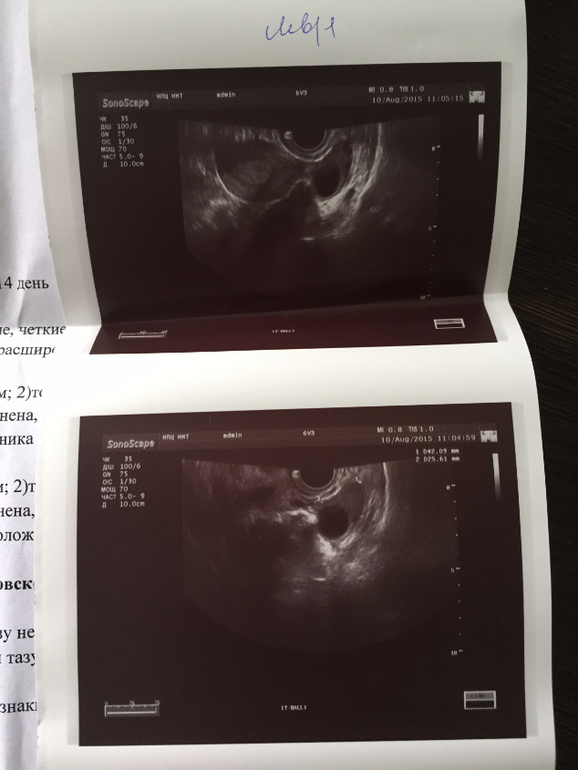

Девочки, сходила сегодня на фолликулогенез! с опозданием правда, гинеколог назначила с 10 дня. а я забегалась по работе и очухалась только в субботу-на 12день. А записалась только на сегодня-14 день! И успела и не прогадала, Господи дай мне сил))) Я на этот доминантный фолликул не нарадуюсь! Будто он уже и есть кроха моя! С моими мультифол. яичниками,как тут не радоваться))) В левом растет он,мой хороший и вот-вот должна быть О. Правый заполонили мои мультики(

И мне впервые сказали,что М-Эхо хорошее! Это еще дало мне сил! Все у меня получится!